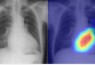

Meanwhile, chest radiography is one of the most common tests to identify diseases, primarily of the lungs. Even though the heart is also visible in chest radiographs, little was known heretofore about the ability of chest radiographs to detect cardiac function or disease.

Chest radiographs, or chest X-Rays, are performed in many hospitals and very little time is required to conduct them, making them highly accessible and reproducible. Accordingly, the research team led by Dr. Daiju Ueda, from the Department of Diagnostic and Interventional Radiology at the Graduate School of Medicine of Osaka Metropolitan University, reckoned that if cardiac function and disease could be determined from chest radiographs, this test could serve as a supplement to echocardiography.

Dr. Ueda’s team successfully developed a model that utilizes AI to accurately classify cardiac functions and valvular heart diseases from chest radiographs. Since AI trained on a single dataset faces potential bias, leading to low accuracy, the team aimed for multi-institutional data.

The AI model was able to categorize precisely six selected types of valvular heart disease, with the Area Under the Curve, or AUC, ranging from 0.83 to 0.92. (AUC is a rating index that indicates the capability of an AI model and uses a value range from 0 to 1, with the closer to 1, the better.) The AUC was 0.92 at a 40% cut-off for detecting left ventricular ejection fraction—an important measure for monitoring cardiac function.